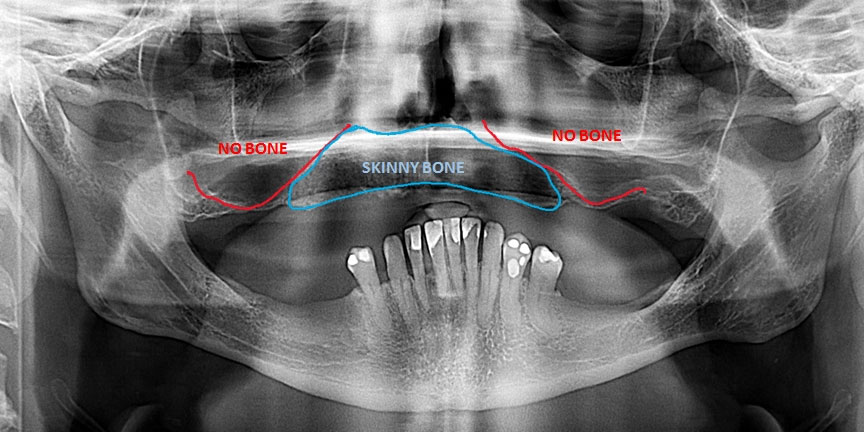

Difficult Cases

We treat patients when other providers cannot manage. CLICK HERE

Severe Bone Loss